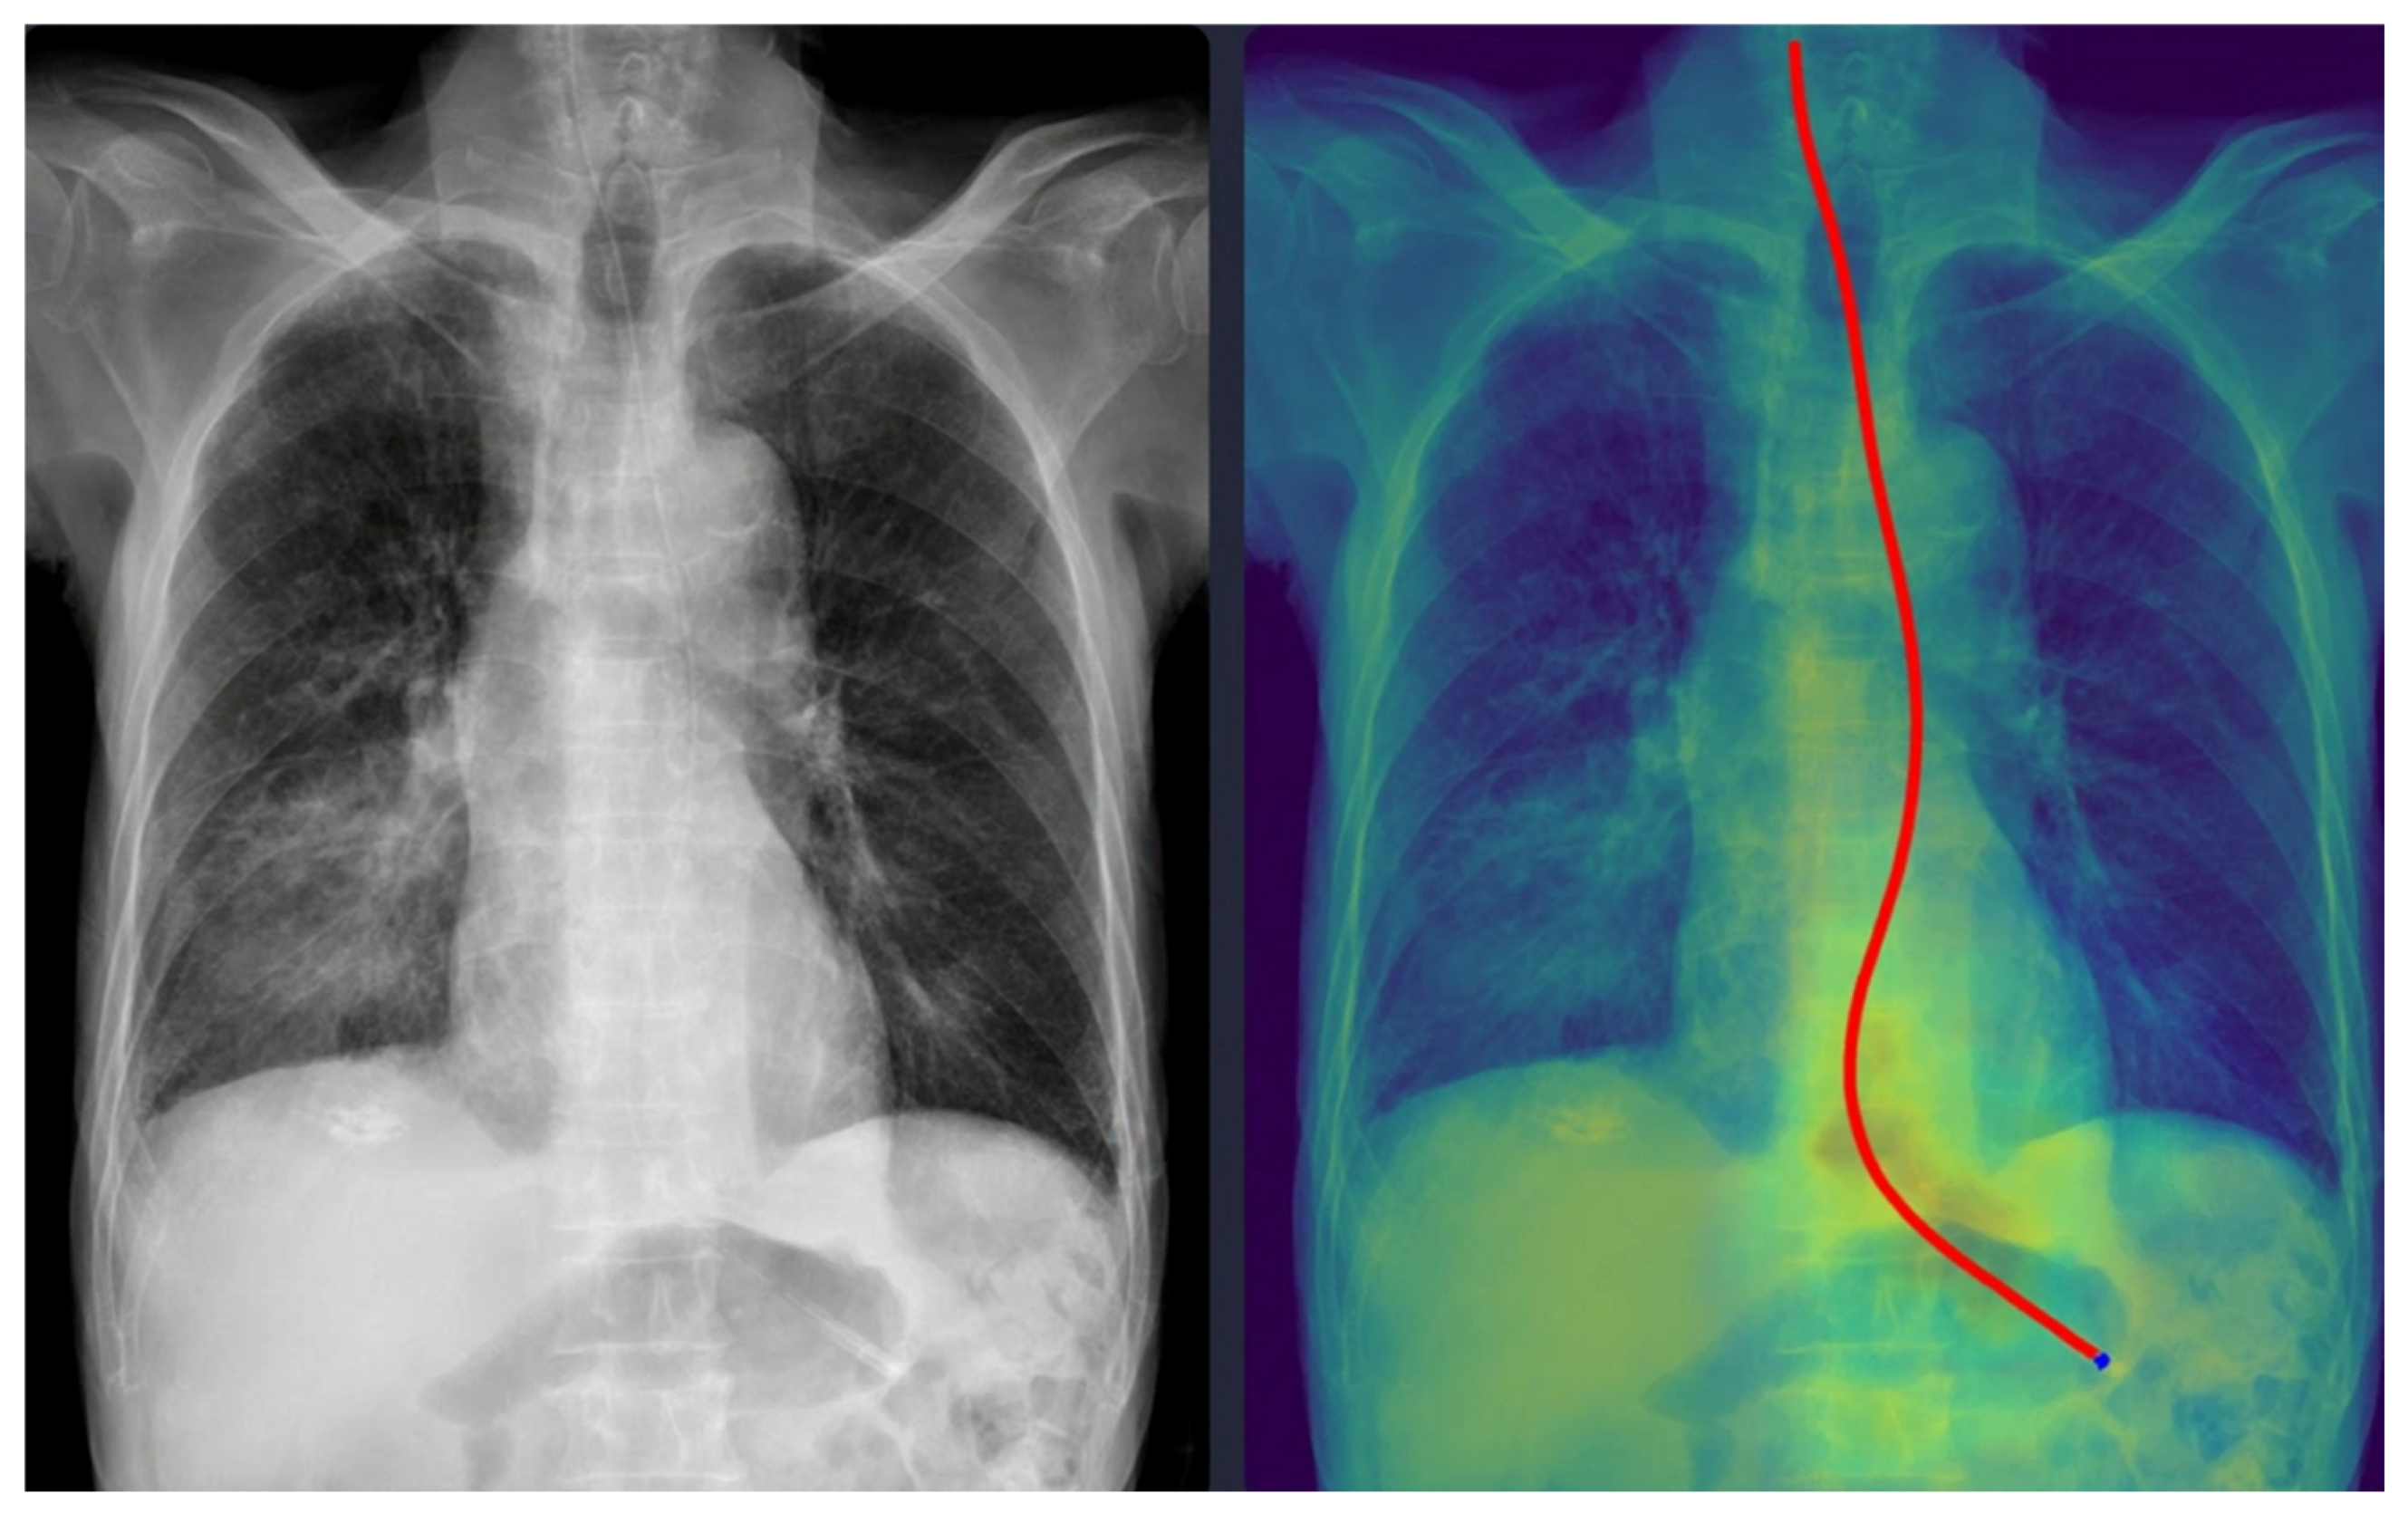

Representative examples of misclassified cases are shown in Figure 2 and Figure 3. The most critical failure involved an NG tube coiled at the indicated site in Figure 2, which suggested incomplete placement and a significant safety risk. The DL model misclassified this case as ‘complete’ based solely on the position of the tip projected below the gastroesophageal junction. Technically, this false-positive classification was highly likely due to the scarcity of such complex, coiled morphological features in the training dataset. While the segmentation module correctly identified the general tube structure, the dual-stage model failed to recognize this pronounced looping or coiling as an immediate risk factor, resulting in the classification module overriding the critical incomplete placement status. This finding identifies a crucial, previously unanticipated failure mode in the model’s design and carries substantial clinical significance, as initiating feeding through a coiled tube presents a high risk of aspiration pneumonia. Moving forward, efforts must focus on incorporating a greater diversity of these rare, yet clinically critical, coiled cases into the dataset to enhance the robustness of the tube segmentation process, thereby ensuring improved and safer clinical implementation. In Figure 3, the DL model failed to draw the entire trajectory of the NG tube and misclassified a complete case as incomplete. A representative example of a correctly classified case is shown in Figure 4. The tip of the NG tube is placed under the gastroesophageal junction and is safe to feed. Because most cases were correctly positioned (=95%), prevalence bias likely inflated the AC1 coefficient, and κ was lower despite near-identical classifications. Future studies should include more incomplete cases to obtain stable reliability estimates [12]. Prevalence-adjusted bias-adjusted kappa (PABAK) estimates were also evaluated with bootstrapping confidence intervals [13]. The results of the agreement among physicians and the DL model are shown in Table 4. Cohen’s κ showed the smallest estimate of 0.644 (95% confidence interval (CI): 0.366–0.922), which increased when using PABAK (0.911 (95% CI: 0.812–0.967)) and Gwet’s AC1 coefficient (0.956 (95% CI: 0.907–0.991)).

4.1. Failure Case Analysis and Safety Implications

Although the physicians agreed in all cases, six cases were discordant between the physicians and the DL model. One case was misclassified as ‘complete’ despite the NG tube being incompletely inserted (coiled), which could have been potentially fatal. As shown in Figure 2, the model interpreted it as complete because the tip of the NG tube was projected below the gastroesophageal junction level. The standalone Gradient-weighted Class Activation Mapping (Grad-CAM)-based heatmap and standalone segmentation-derived probability map are shown separately in Supplementary Figure S1. This figure demonstrates the interpretability of our model, which provides images of both maps overlaid together.

Technical and Clinical Analysis: Technically, this error likely stems from the models’ reliance on the vertical coordinate of the tube tip in the 2D projection. While the segmentation module correctly identified the tube structure, the classification head failed to recognize the “coiling” or “looping” morphological feature as a risk factor, likely due to the scarcity of such anomalous patterns in the training dataset. Clinically, initiating feeding through a coiled tube can lead to aspiration pneumonia. This failure mode highlights the inherent limitation of image-level classification models when dealing with complex 3D spatial configurations compressed into 2D images.

Safety Recommendations: To mitigate this risk, we emphasize that the DL model must strictly function as a “second reader” for trajectory visualization rather than a binary decision maker. In clinical practice, physicians must verify the Grad-CAM-based heatmap or segmentation mask overlaid on the original image. If the heatmap shows any deviation from a linear esophageal path (e.g., widening, looping), the placement must be flagged for manual review regardless of the high probability score. This aligns with the current paradigm of human–AI collaboration, where DL tools act as augmentative aids that enhance efficiency while maintaining physician oversight to ensure patient safety [21].

Figure 2. A misclassified incomplete nasogastric tube case identified as complete by the model. The arrow indicates the coiled portion of the nasogastric tube. The red line represents the trajectory of the nasogastric tube, and the blue dot indicates the tip of the nasogastric tube as identified by the deep learning model.